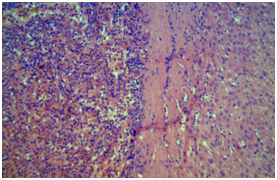

Male, 47 years old, with an incidental finding of hepatic lesion, during investigation of nephrolithiasis. Previous history of splenectomy after abdominal trauma due to automobile accident 20 years ago. Hypertensive in use Olmesartan, denied other pathologies and surgeries. On physical examination: good general condition, anicteric, painless abdomen, without palpable masses. Laboratory tests: Hb 14g/dL (13,5 - 17,5), Hct 44,4% (39 - 55), Platelets 268,000/mm3 (150.000 - 400.000), creatine 0,9mg/dL (1,5), INR 0,8, CEA 1,33 ng/mL (<3,0), CA 19-9 20U/mL (<37), AFP 1,5ng/dl (<7,22 ), albumin 4,19g/dL (3,4 – 4,8), AST 20U/L (17 - 55), ALT 18U/L (21-71), GGT 54U/L (15/73), AP 48U/L (38 - 126), total bilirrubin 0,57mg/dL (0,2 – 1,3). MRI showed nodular hepatic lesion, 42x41x28mm, slight hyperintense in T2, with contrast enhancement and washout in late phase, in segment II, without dilatation of biliary tract (Figures 2). The initial diagnosis was hepatic adenoma. Proceeded with hepatic segmentectomy, with good evolution. The surgical specimen referred to pathological anatomy and revealed hepatic splenosis (Figures 1).

Figure 1 Ectopic splenic tissue in hepatic parenchyma (Fig A 20x; Fig B and C 40x).

Splenosis, one type of manifestation of ectopic spleen tissue,2 is a heterotopic autotransplantation of splenic tissue (Figure 1), generally after abdominal trauma or surgical intervention,6 and in this reported case the patient was also submitted to splenectomy after abdominal trauma. The first case of splenosis was reported in the English literature in 1939 by Buchbinder and Lipkoff.11 In 2014, Naoya Sato et al.4 described the first case of hepatic splenosis without previous abdominal trauma or surgery.4

The keys to diagnose intrahepatic splenosis are knowledge of splenic injury, the subcapsular location of the lesion (mostly in the left liver lobe), and the association with other hypervascular intraperitoneal lesions.22 If intrahepatic splenosis is suspected, technetium-99m–labeled red blood cell scintigraphy should be performed and represents the most specific imaging technique.8,22,23 Histology represents the gold standard for the diagnosis.8,24 Sometimes, laparoscopy is necessary for biopsy. Histologically, liver splenosis presents as nodular lesions rich in lymphoid tissue and hematopoietic cells, no hilus and its blood supply is derived from surrounding tissues and vessels (Figure 3).5,12 Due to the lack of adequate reported cases, there's no consensus on a gold standard diagnostic approach to hepatic splenosis.14